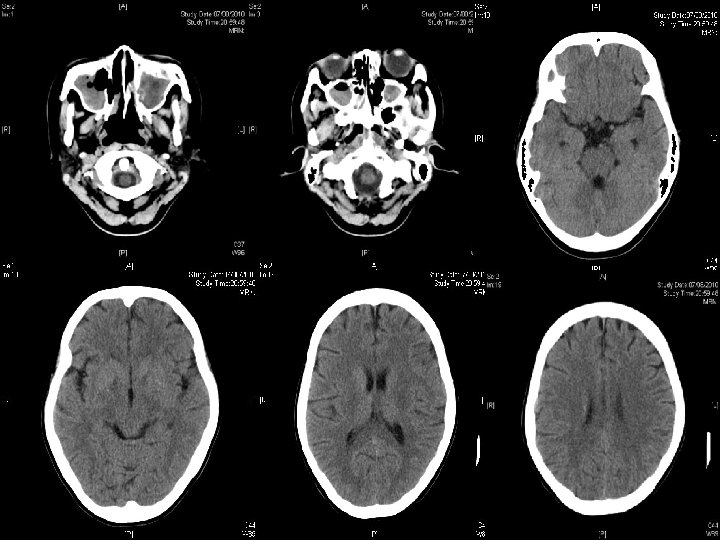

Unexpected problems (3) Seen by eye for increasing redness Right endophthalmitis diagnosed 25 th Aug Bedside Intravitreous Vancomycin + Amikacin performed n CT orbit 25 th Aug Increased Rt vitreous chamber hypodensities at bilateral basal ganglia n

Contrast CT brain on 27 th Aug

Searching for an answer, again…. . n n n n n 9 th July: Plain CT Brain (Hospital A) 7 th Aug: Plain CT Brain (Hospital A) 25 th August: Plain CT Orbit (Hospital A) 27 th August: Contrast CT brain + Sinus 4 th September: MRI brain + brainstem 4 th September: Plain CT brain 10 th September: Contrast CT brain 11 th September: Plain CT sinus 15 th September: MRI brain + DWI

Summary of progression • June/ 2010 n • July/ 2010 n • Early Aug/ 2010 n • Late Aug/ 2010 n • Sept/ 2010 n Lt face weak Bulbar palsy Dilated Rt pupil and uveitis Endophthalmitis and high fever Deep coma, tetraplegia, high fever n n n Nil imaging Facial neuritis Bilateral basal ganglia change Bilateral temporal + BG + thalami + pons